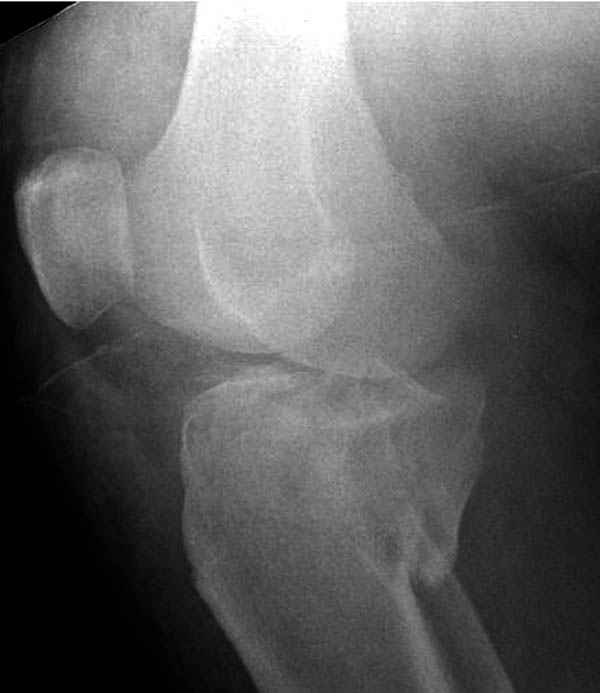

Пациенту сделали КТ - ухитрились сделать на шине Белера (не давал положить прямую ногу) - срезали передний отдел. Планируется на пятницу (24.12) на операцию - синтез длинной мыщелковой LCP-пластиной Synthes :). Отек ближе к слову умеренный (окружность голени +4 см по сравнению со здоровой). КТ и снимок на вытяжении прилагаются.

Трудно поверить, что разрекламированная Ортопедическая школа Восточной Украины позволяет такие странные снимки? На прямом снимке сохранен общий контур плато, но не известна судьба импрессии суставной поверхности. На полубоковой?, оставлен без репозиции задне-медиальный отдел, и навряд ли после такой фиксации можно удовлетвориться результатом.

Такая ситуация характерна для многих, когда принимается ошибочное решение, т.е пытаются фиксировать одним имплантом переломы двух мыщелков. Латеральная пластина приемлема только для тех случаев, когда сохраняется интактным медиальный диафизарный кортекс и отсутствует фрагментация на верхушке медиального перелома.

Здесь как раз тот случай, когда результат зависит не только от мастерства хирурга, но и от наличия современных методов исследования. Например, КТ которая поможет рассчитать направления шурупов и установку импланта. Кроме этого, поможет определиться с доступом.